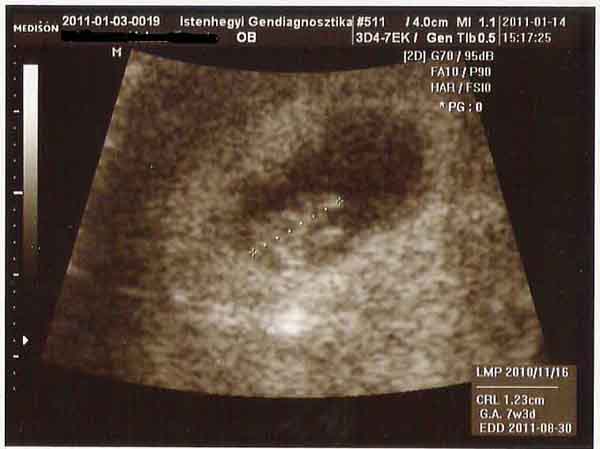

Jó estét! Szeretnék bemutatni nektek valakit. 12 mm és úgy zakatol a kis szíve mint egy gőzmozdony. Hallhattuk is, sőt megnézte a doki és egészséges a szívhangja és a pulzusa. 1 héttel fiatalabb a számoltnál, azért nem találtuk eddig a kis babszemet.

kisbeeka: Bizony béna. Most ahogy az UH-fej a hasamhoz ért azonnal látszott a kis szarosom a képernyőn. A doki is nagyon aranyos volt. Egyből megismert és már úgy állt hozzá, hogy most már látni fogjuk. Még 4D-ben is megmutatta, de azért azon még nem sok minden látszott. :D

Át is kalibráltam a babakocsit. Érdekes ez a vonalzó eddig 8+4 voltam és 207 nap volt hátra. Most 7+3 vagyok és 228 nap van hátra. Nekem egy hét 7 napból áll..... :shock: